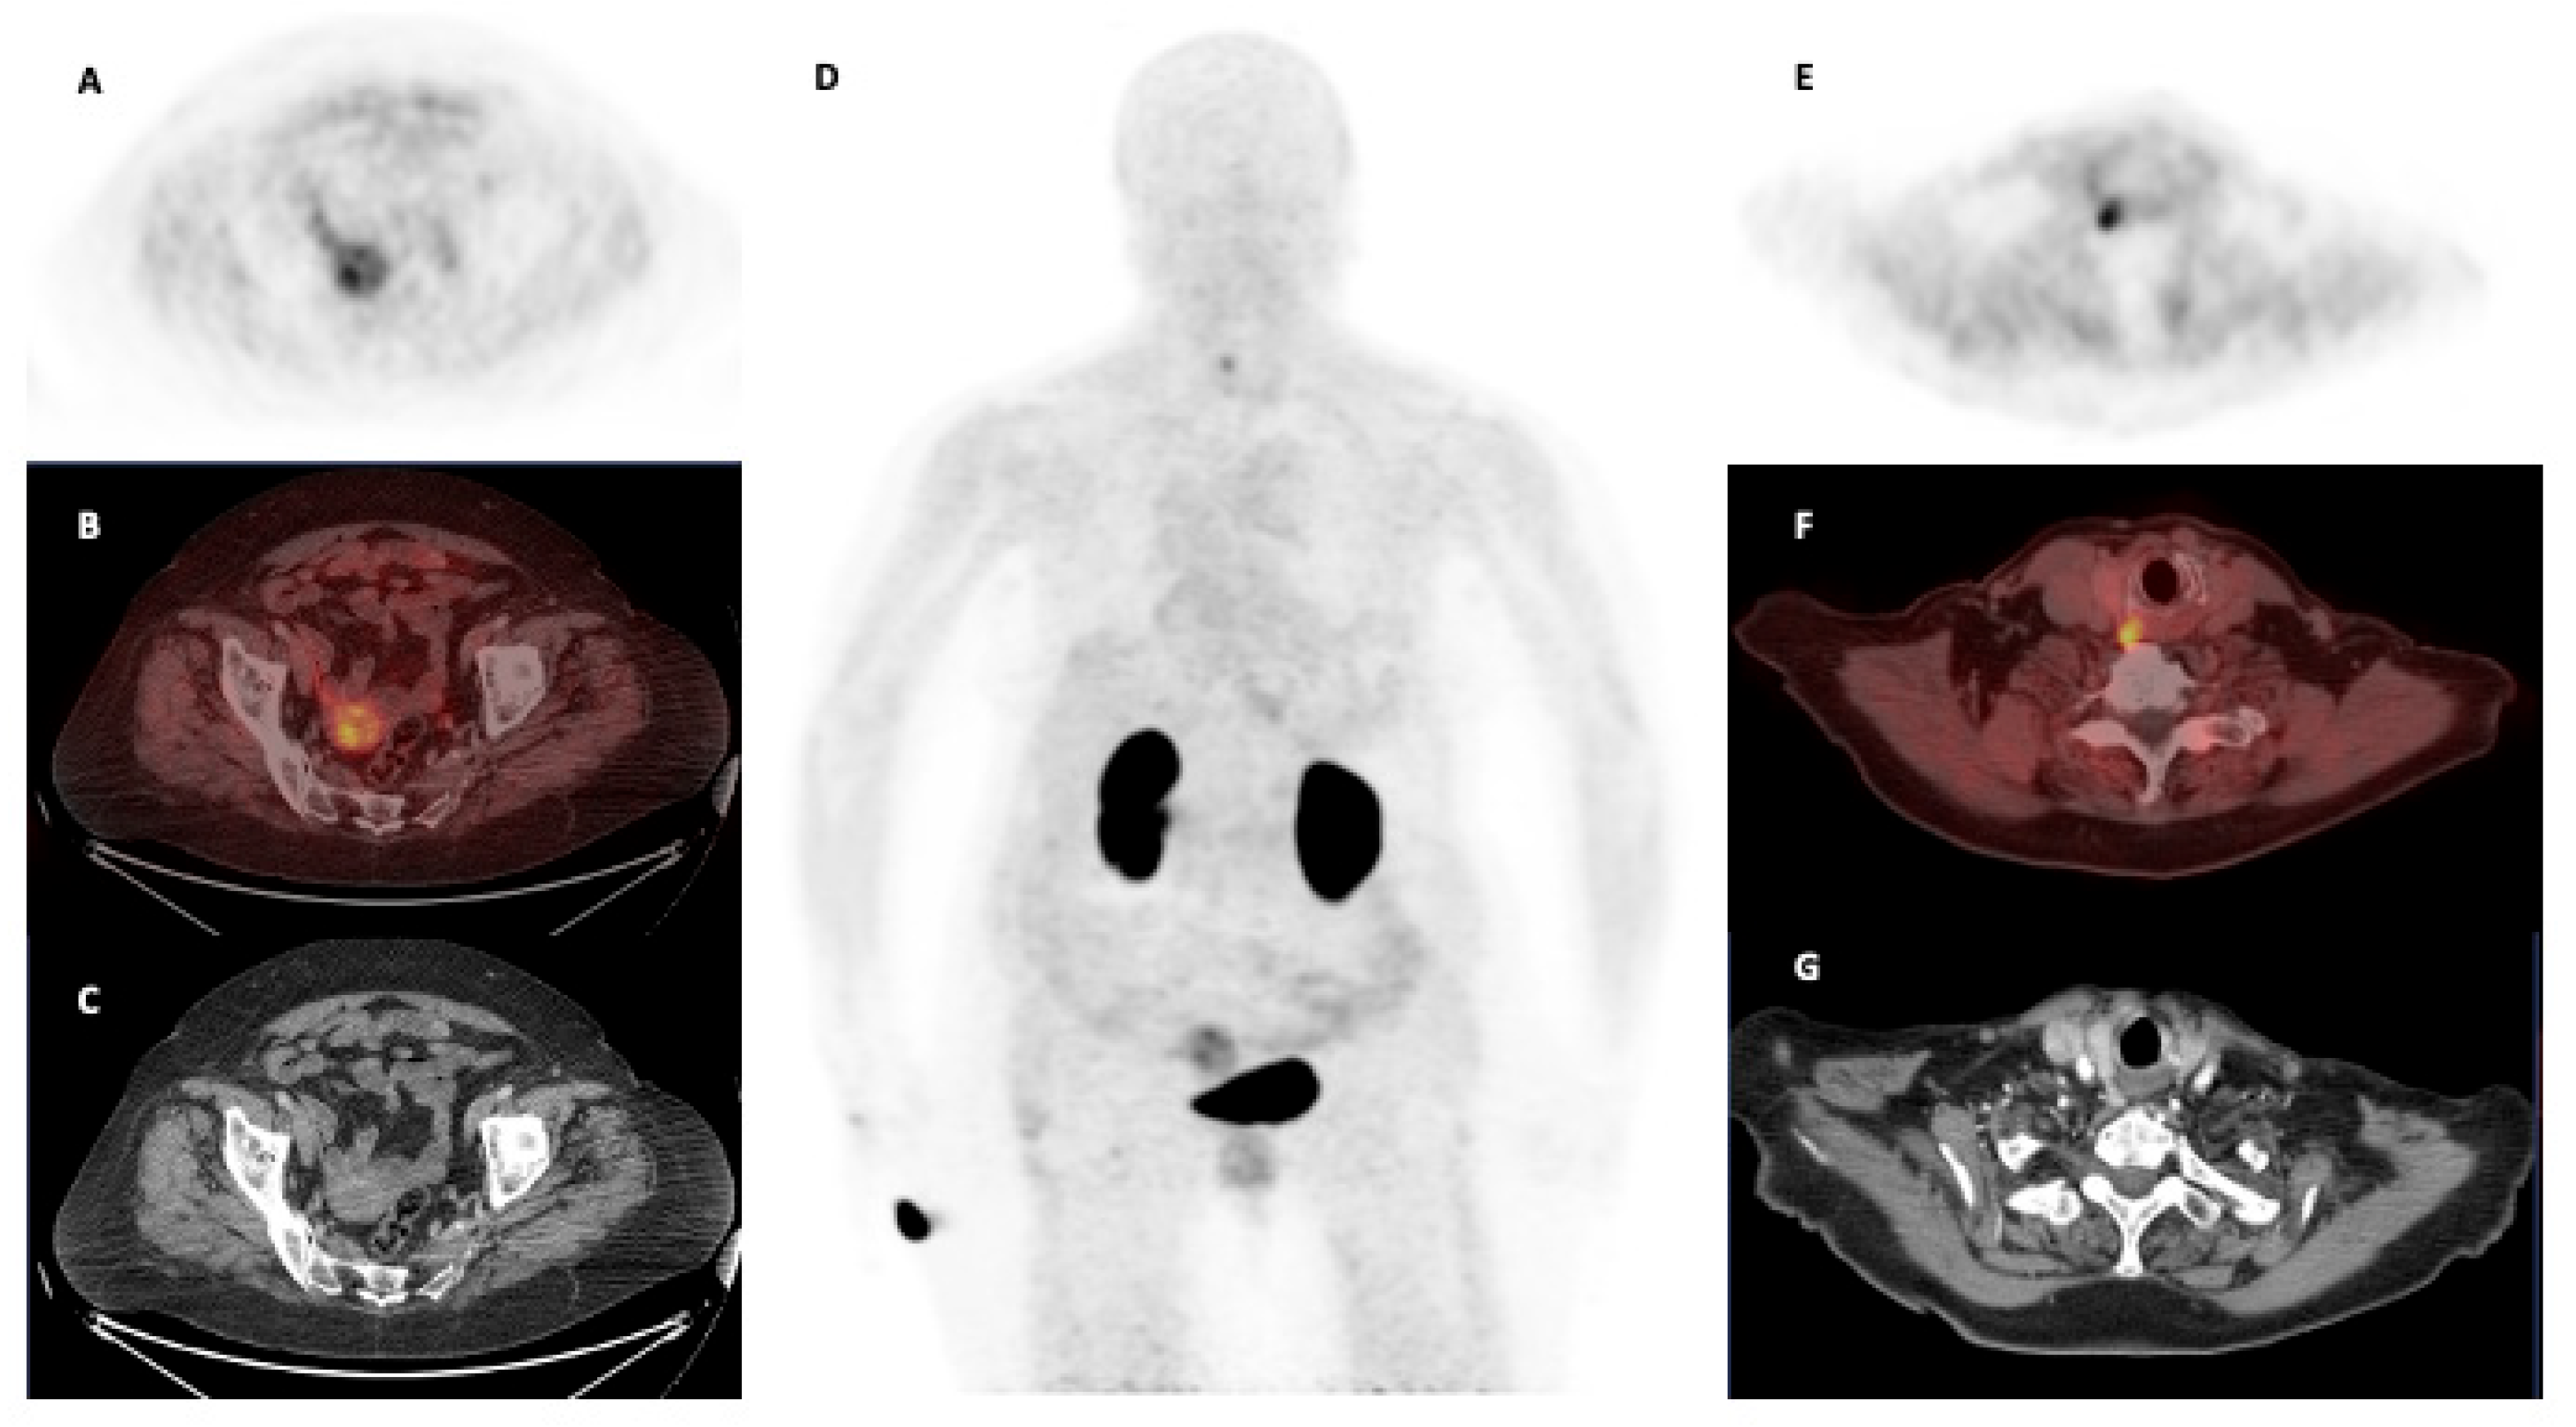

| Singh et al. [45] | India | 2024 | Oncological | Ovarian carcinoma | 1 | – | – | [68Ga]Ga-Trivehexin PET/CT may be useful to define disease extension in metastatic ovarian carcinoma. |